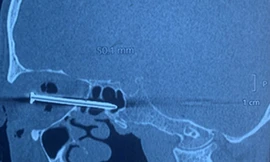

TPO - Một nam thanh niên có tiền sử bị bệnh tâm thần phân liệt – rối loạn lo âu, sợ hãi và đang điều trị thuốc đã bất ngờ dùng muỗng nhựa tự đâm vào hốc mắt của mình dẫn đến vết thương xuyên sọ, vừa được phẫu thuật cứu sống thành công.